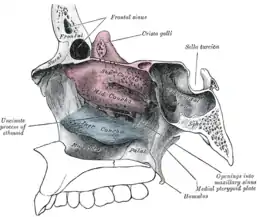

Lateral wall of nasal cavity, showing ethmoid bone in position. (Superior and middle in pink, and inferior in blue.) | |

The superior conchae are smaller structures, connected to the middle conchae by nerve-endings, and serve to protect the olfactory bulb. The superior conchae attach to the ethmoid bone. The openings to the posterior ethmoidal sinuses exist under the superior meatus.[3] The sphenoid sinus ostium exists medial to the superior turbinate.[5]

The middle conchae are smaller but have the most complex anatomy of the nasal turbinates. They originate from the lateral edge of the cribriform plate of the ethmoid bone. They insert anteriorly into the frontal process of the maxilla and posteriorly into the perpendicular plate of the palatine bone.[6] There are three mutually perpendicular segments of the middle turbinate: from proximal to distal, there is the horizontal segment (axial plane), the basal lamella (coronal plane), and the vertical segment (sagittal plane). They project downwards over the openings of the maxillary and anterior and middle ethmoid sinuses, and act as buffers to protect the sinuses from coming in direct contact with pressurized nasal airflow. Most inhaled airflow travels between the inferior concha and the middle meatus.[3] In humans, they are usually as long as the little finger.